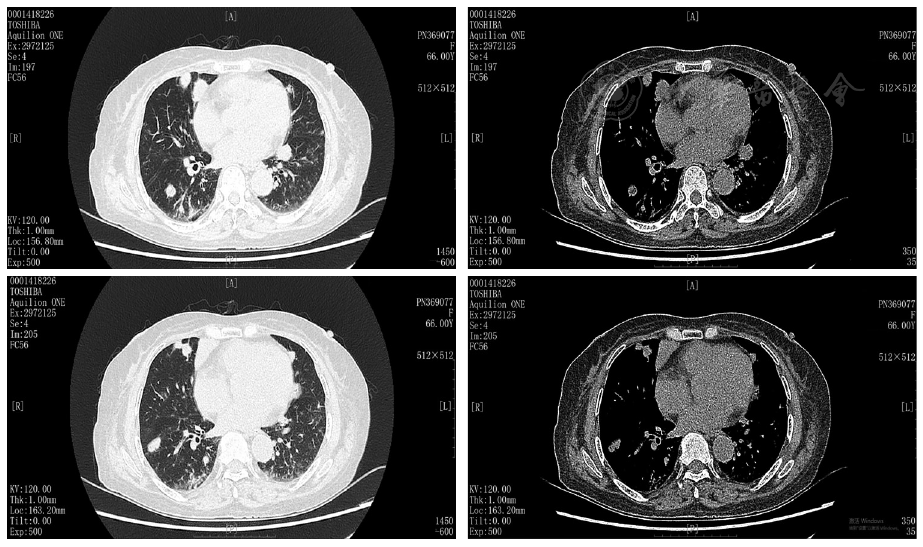

A 66-year-old female presented with fever, cough, and cutaneous nodular ecchymosis. The comprehensive examination revealed multiple nodules in both lungs, mediastinal lymphadenopathy, and splenomegaly; blood routine test: white blood cell count 2.15×109/L, hemoglobin 77 g/L, platelet count 67×109/L; C-reactive protein (CRP) 24.98 mg/L, erythrocyte sedimentation rate 35mm/1 h, ferritin>2 000.00μg/L, interleukin-2 receptor 7 500.00 U/ml, Epstein-Barr virus quantification positive, hepatitis B surface antigen, hepatitis B e antibody, and hepatitis B core antibody positive; bronchoalveolar lavage fluid next-generation sequencing(NGS) indicated Epstein-Barr virus positivity; bone marrow aspiration showed decreased platelet count and a bone marrow picture. Lung tissue biopsy immunohistochemistry (IHC) shows CD20(+ ) and Ki-67(+ ). Special stains: PAS (-) and PASM (-). In situ hybridization: EBER (+ ). The final pathological diagnosis suggests lymphomatoid granulomatosis cannot be excluded. The final diagnosis included HPS, PLG, EBV infection, chronic hepatitis B, and pulmonary infection. Initial treatment with anti-infectives, anti-inflammatory agents, and antivirals led to symptomatic improvement. However, the patient experienced recurrent pulmonary infections post-discharge. Ten months after onset, she was readmitted for fever and cough, and repeat lung biopsy confirmed B-cell lymphoma, prompting referral to hematology.